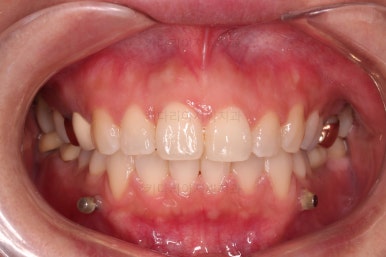

장치 부착 직후의 얼굴 모습인데요.

입이 얼마나 나오는지에, 웃을 때 보이는 브라켓의 모습은 어떤지 참고해 주세요.

이번 환자분은 브라켓을 부착했다고 해서 입이 거의 나오지 않는 경우였어요.

이처럼 입이 얼마나 나올지는 사람마다 매우 달라서 일단 붙여봐야 아는 경우가 많답니다.

전후 사진을 비교해 볼게요.

6개월만에 부산부분치아교정 완료했어요.

치열도 가지런해졌고, 웃는 모습도 매우 좋아졌네요.